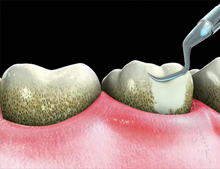

Detartrajul reprezinta una din cele mai importante proceduri ale tratamentului bolii parodontale. Detartrajul manual presupune folosirea unor instrumente cu ajutorul carora se indeparteaza depozitele dure de tartru de pe suprafetele dentare prin miscari de tractiune-impingere-apasare, in functie de instrumentul folosit.

Tartrul este considerat un factor iritativ local, si din aceasta cauza trebuie indepartat periodic, in scop preventiv si curativ, de pe suprafetele coroanelor si radacinilor.